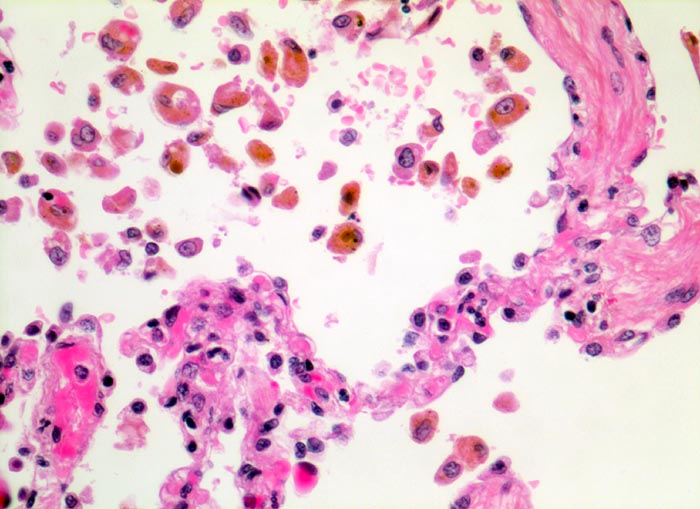

PathoPic – image database / PathoPic ID 5040 - chronische Lungenstauung: Herzfehlerzellen

chronische Lungenstauung: Herzfehlerzellen

Die Alveolarsepten sind deutlich fibrotisch verdickt. Gleichzeitig ist die Gefässausstattung vermindert. Die aus den Kapillaren in die Alveolarräume ausgetretenen Erythrozyten werden von Alveolarmakrophagen phagozytiert. Die Makrophagen enthalten teils intakte Erythrozyten, teils braunes Hämosiderinpigment aus bereits abgebauten Erythrozyten.

Patient mit Mitralinsuffizienz.

320